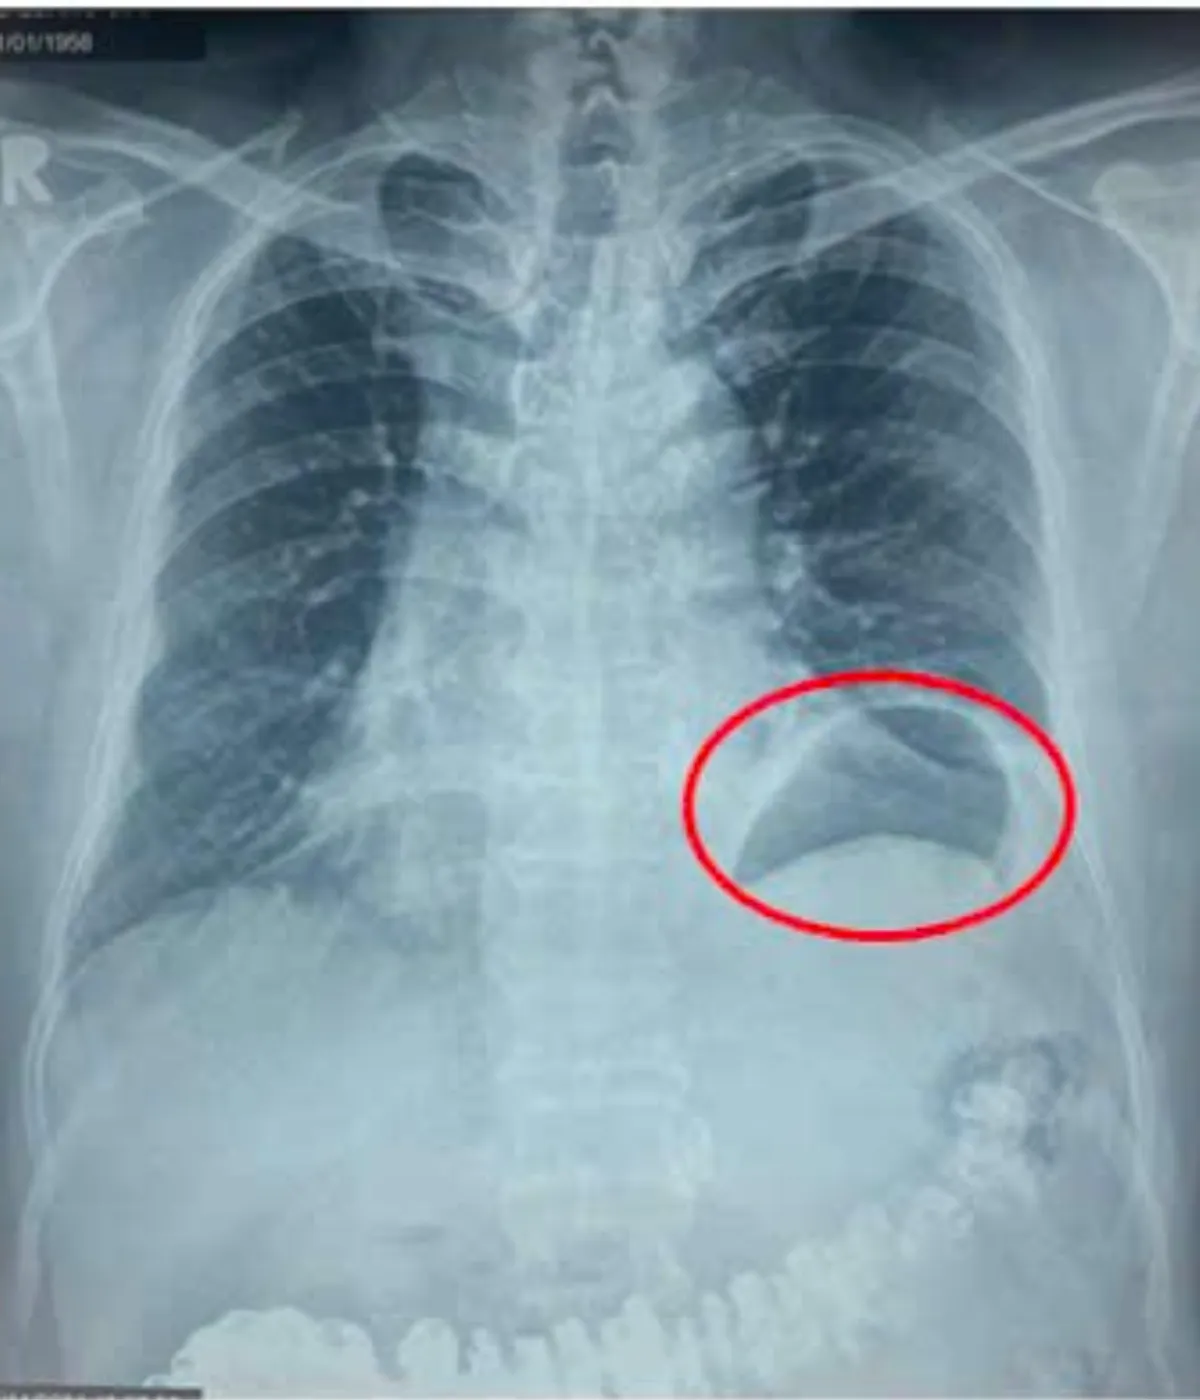

Ông G. cho biết, cách nhập viện khoảng 3 tháng ông thường hay khó thở, thở hụt hơi khi gắng sức, khi vận động hay đi lên cầu thang. Tình trạng này khiến ông không thể vận động thể lực mạnh hay đi bộ tập thể dục với cường độ như trước. Trong đợt khám sức khỏe định kỳ, một bác sĩ khi xem phim X-quang ngực thẳng của ông thì phát hiện vùng phổi bên trái có bất thường và khuyên ông đến Bệnh viện Bình Dân để khám chuyên khoa lồng ngực. Tại Bệnh viện Bình Dân, sau khi thăm khám lâm sàng và xem kết quả chụp X-quang ngực và MSCT-scan ngực, các bác sĩ chẩn đoán ông bị nhão hoành trái với hình ảnh vòm hoành trái nhô cao bất thường. Tình trạng này làm giảm thể tích lồng ngực trái, đây chính là nguyên nhân khiến ông bị khó thở khi gắng sức nhiều tháng nay mà ông không rõ nguyên nhân.

Để chẩn đoán bệnh nhão cơ hoành, liệt cơ hoành, các bác sĩ thường chỉ định người bệnh thực hiện chụp phim X-quang ngực và MSCT-scan ngực. Qua hình ảnh, các chuyên gia có thể thấy cơ hoành bị nâng lên cao hơn so với bình thường. Tuy nhiên, cần phân biệt nhão, liệt hoành với một bệnh lý khác là thoát vị hoành. Thoát vị hoành xảy ra khi có một lỗ khuyết trên cơ hoành, khiến các cơ quan trong bụng như dạ dày, đại tràng có thể chui qua lỗ khuyết lên lồng ngực. Nguyên nhân thường do chấn thương hoặc bẩm sinh. Trong khi đó, nhão cơ hoành, liệt cơ hoành thì cơ quan này không có lỗ khuyết mà chỉ bị giảm đi trương lực của cơ hoành. Điều này khiến khoang bụng đẩy lên trên vùng ngực, khoang lồng ngực bị thu hẹp và tim-phổi bị chèn ép.